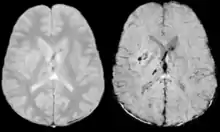

Vascular dementia and cerebral amyloid angiopathy (CAA)

Gradient recalled echo (GRE) imaging is the conventional way to detect hemorrhage in CAA, however SWI is a much more sensitive technique that can reveal many micro-hemorrhages that are missed on GRE images.[7] A conventional gradient echo T2*-weighted image (left, TE=20 ms) shows some low-signal foci associated with CAA. On the other hand, an SWI image (center, with a resolution of 0.5 mm x 0.5 mm x 2.0 mm, projected over 8mm) shows many more associated low-signal foci. Phase images were used to enhance the effect of the local hemosiderin build-up. An example phase image (right) with yet higher resolution of 0.25 mm x 0.25 mm x 2.0 mm shows a clear ability to localize multiple CAA-associated foci.